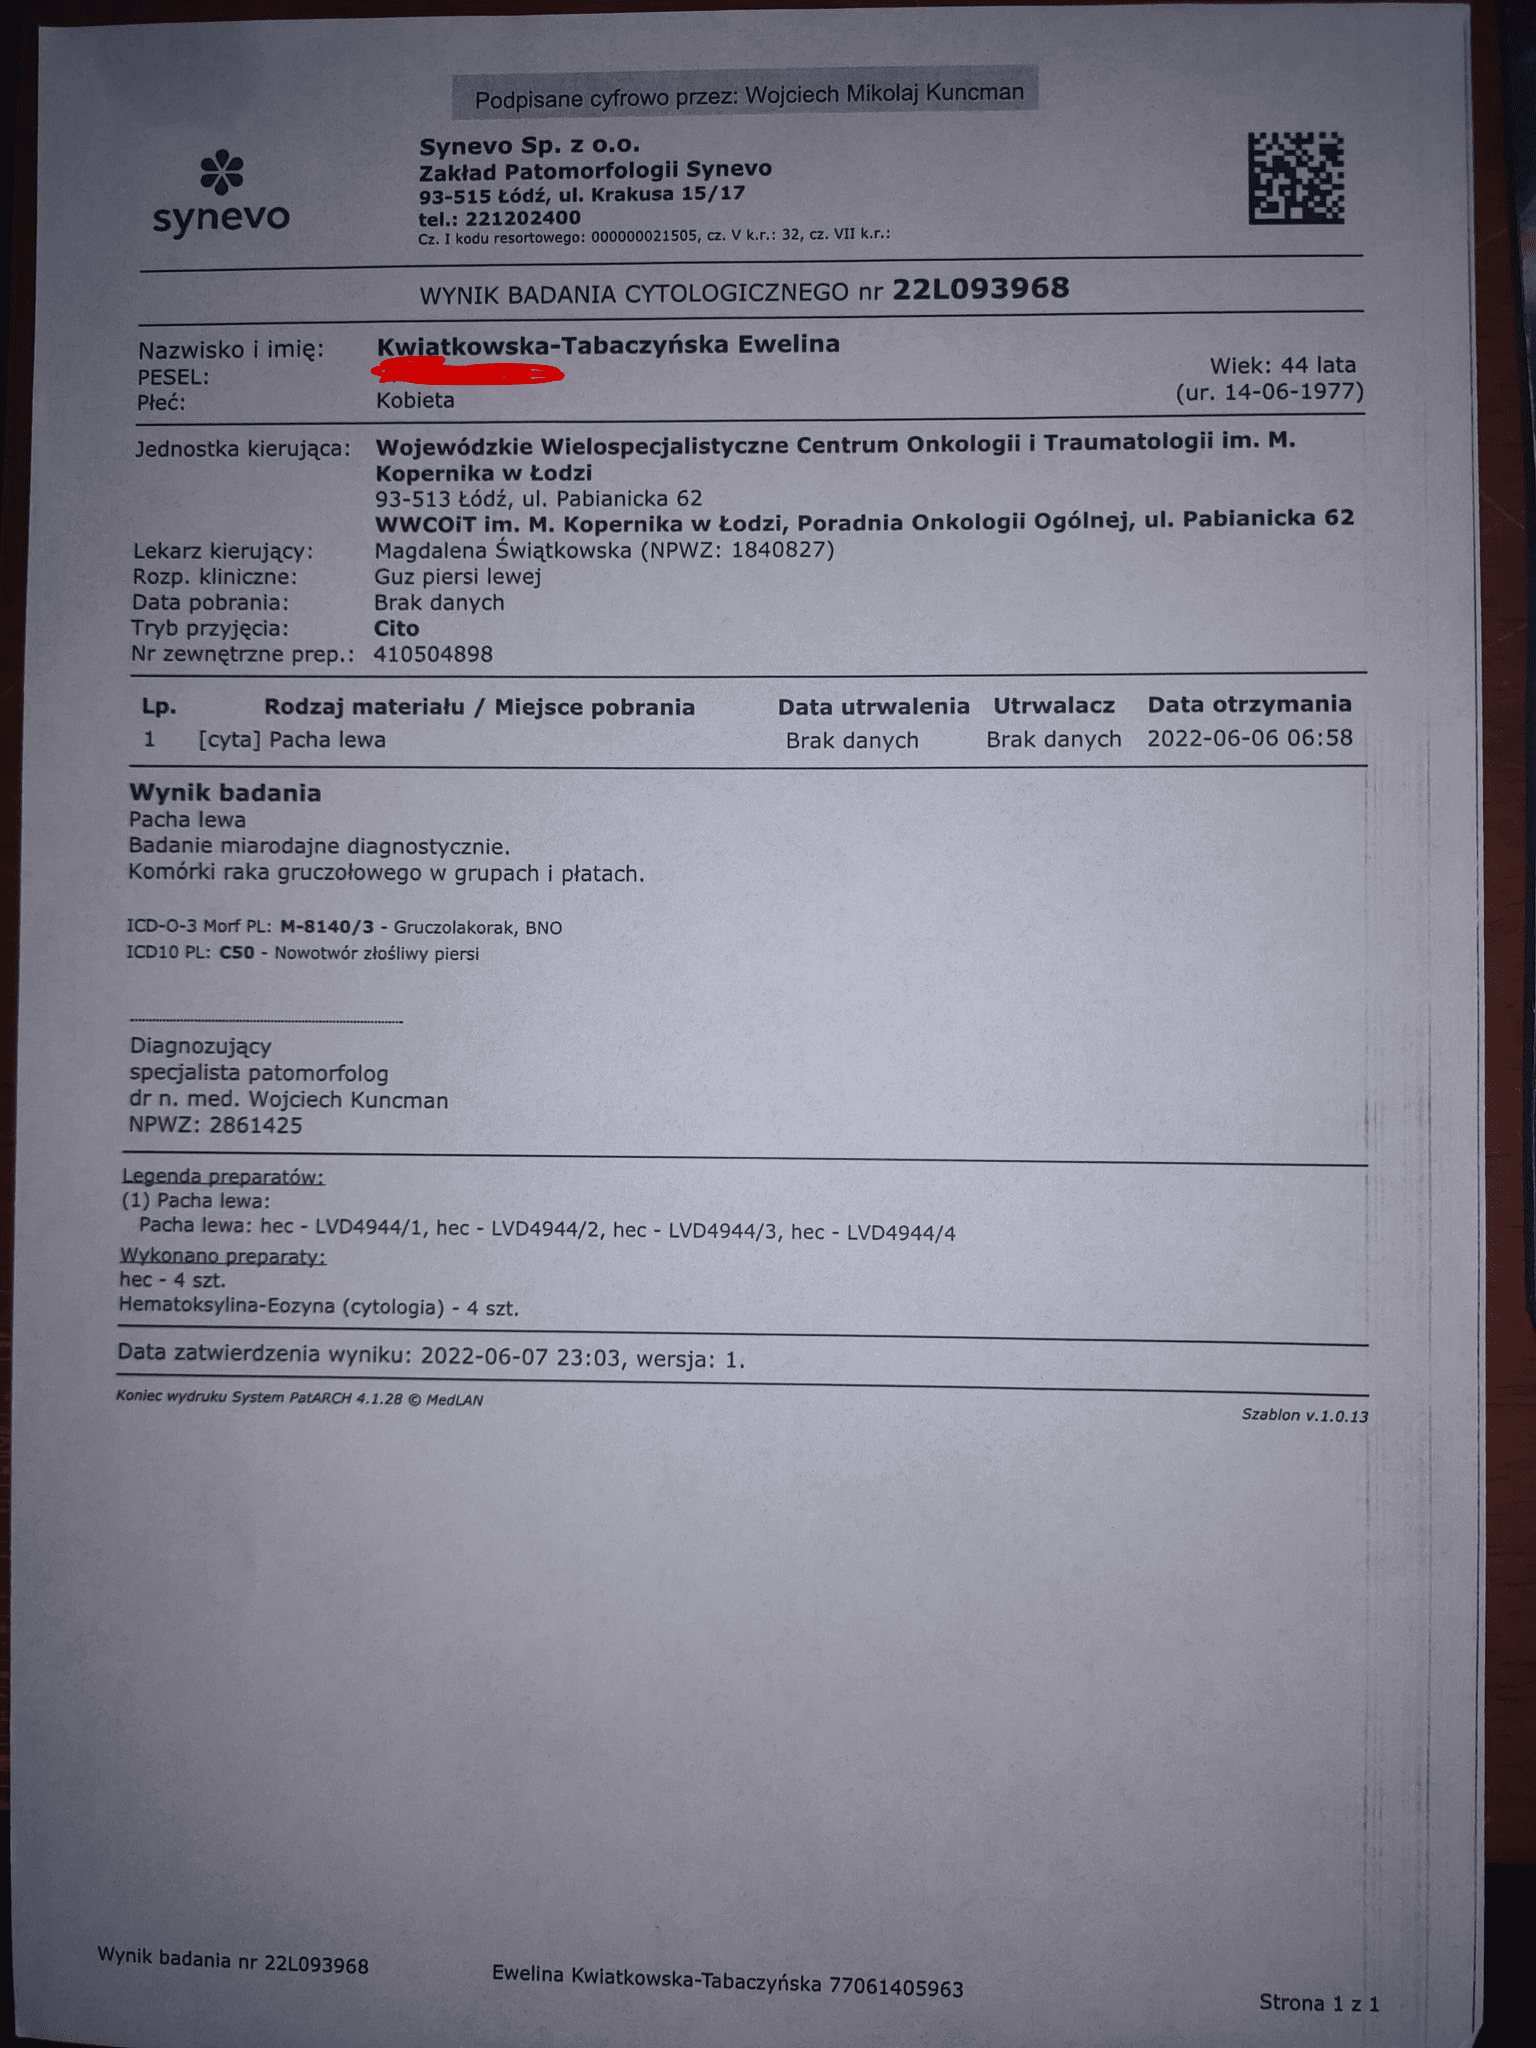

Złośliwy nowotwór piersi, po kolejnych badaniach stwierdzono przerzuty do kości.